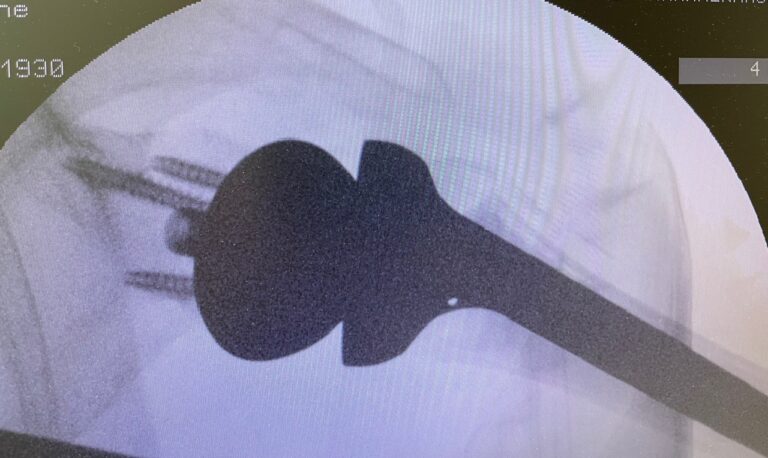

Η ανάστροφη ολική αρθροπλαστική ώμου είναι μια εξειδικευμένη χειρουργική επέμβαση αντικατάστασης της άρθρωσης του ώμου, η οποία εφαρμόζεται κυρίως σε ασθενείς με σοβαρή βλάβη του στροφικού πετάλου και εκφυλισμό της άρθρωσης.

Σε αντίθεση με την κλασική αρθροπλαστική, αλλάζει τη μηχανική του ώμου, επιτρέποντας στο χέρι να κινείται κυρίως με τη δύναμη του δελτοειδούς μυός.

Τι σημαίνει «ανάστροφη» αρθροπλαστική;

Στην ανάστροφη αρθροπλαστική:

- Η κεφαλή τοποθετείται στην ωμογλήνη

- Η κοίλη επιφάνεια τοποθετείται στο βραχιόνιο

Αυτή η αναστροφή επιτρέπει στον δελτοειδή μυ να αναλάβει την κίνηση του ώμου, όταν το στροφικό πέταλο δεν λειτουργεί.

- Περιλαμβάνει τοποθέτηση ειδικής πρόθεσης ώμου